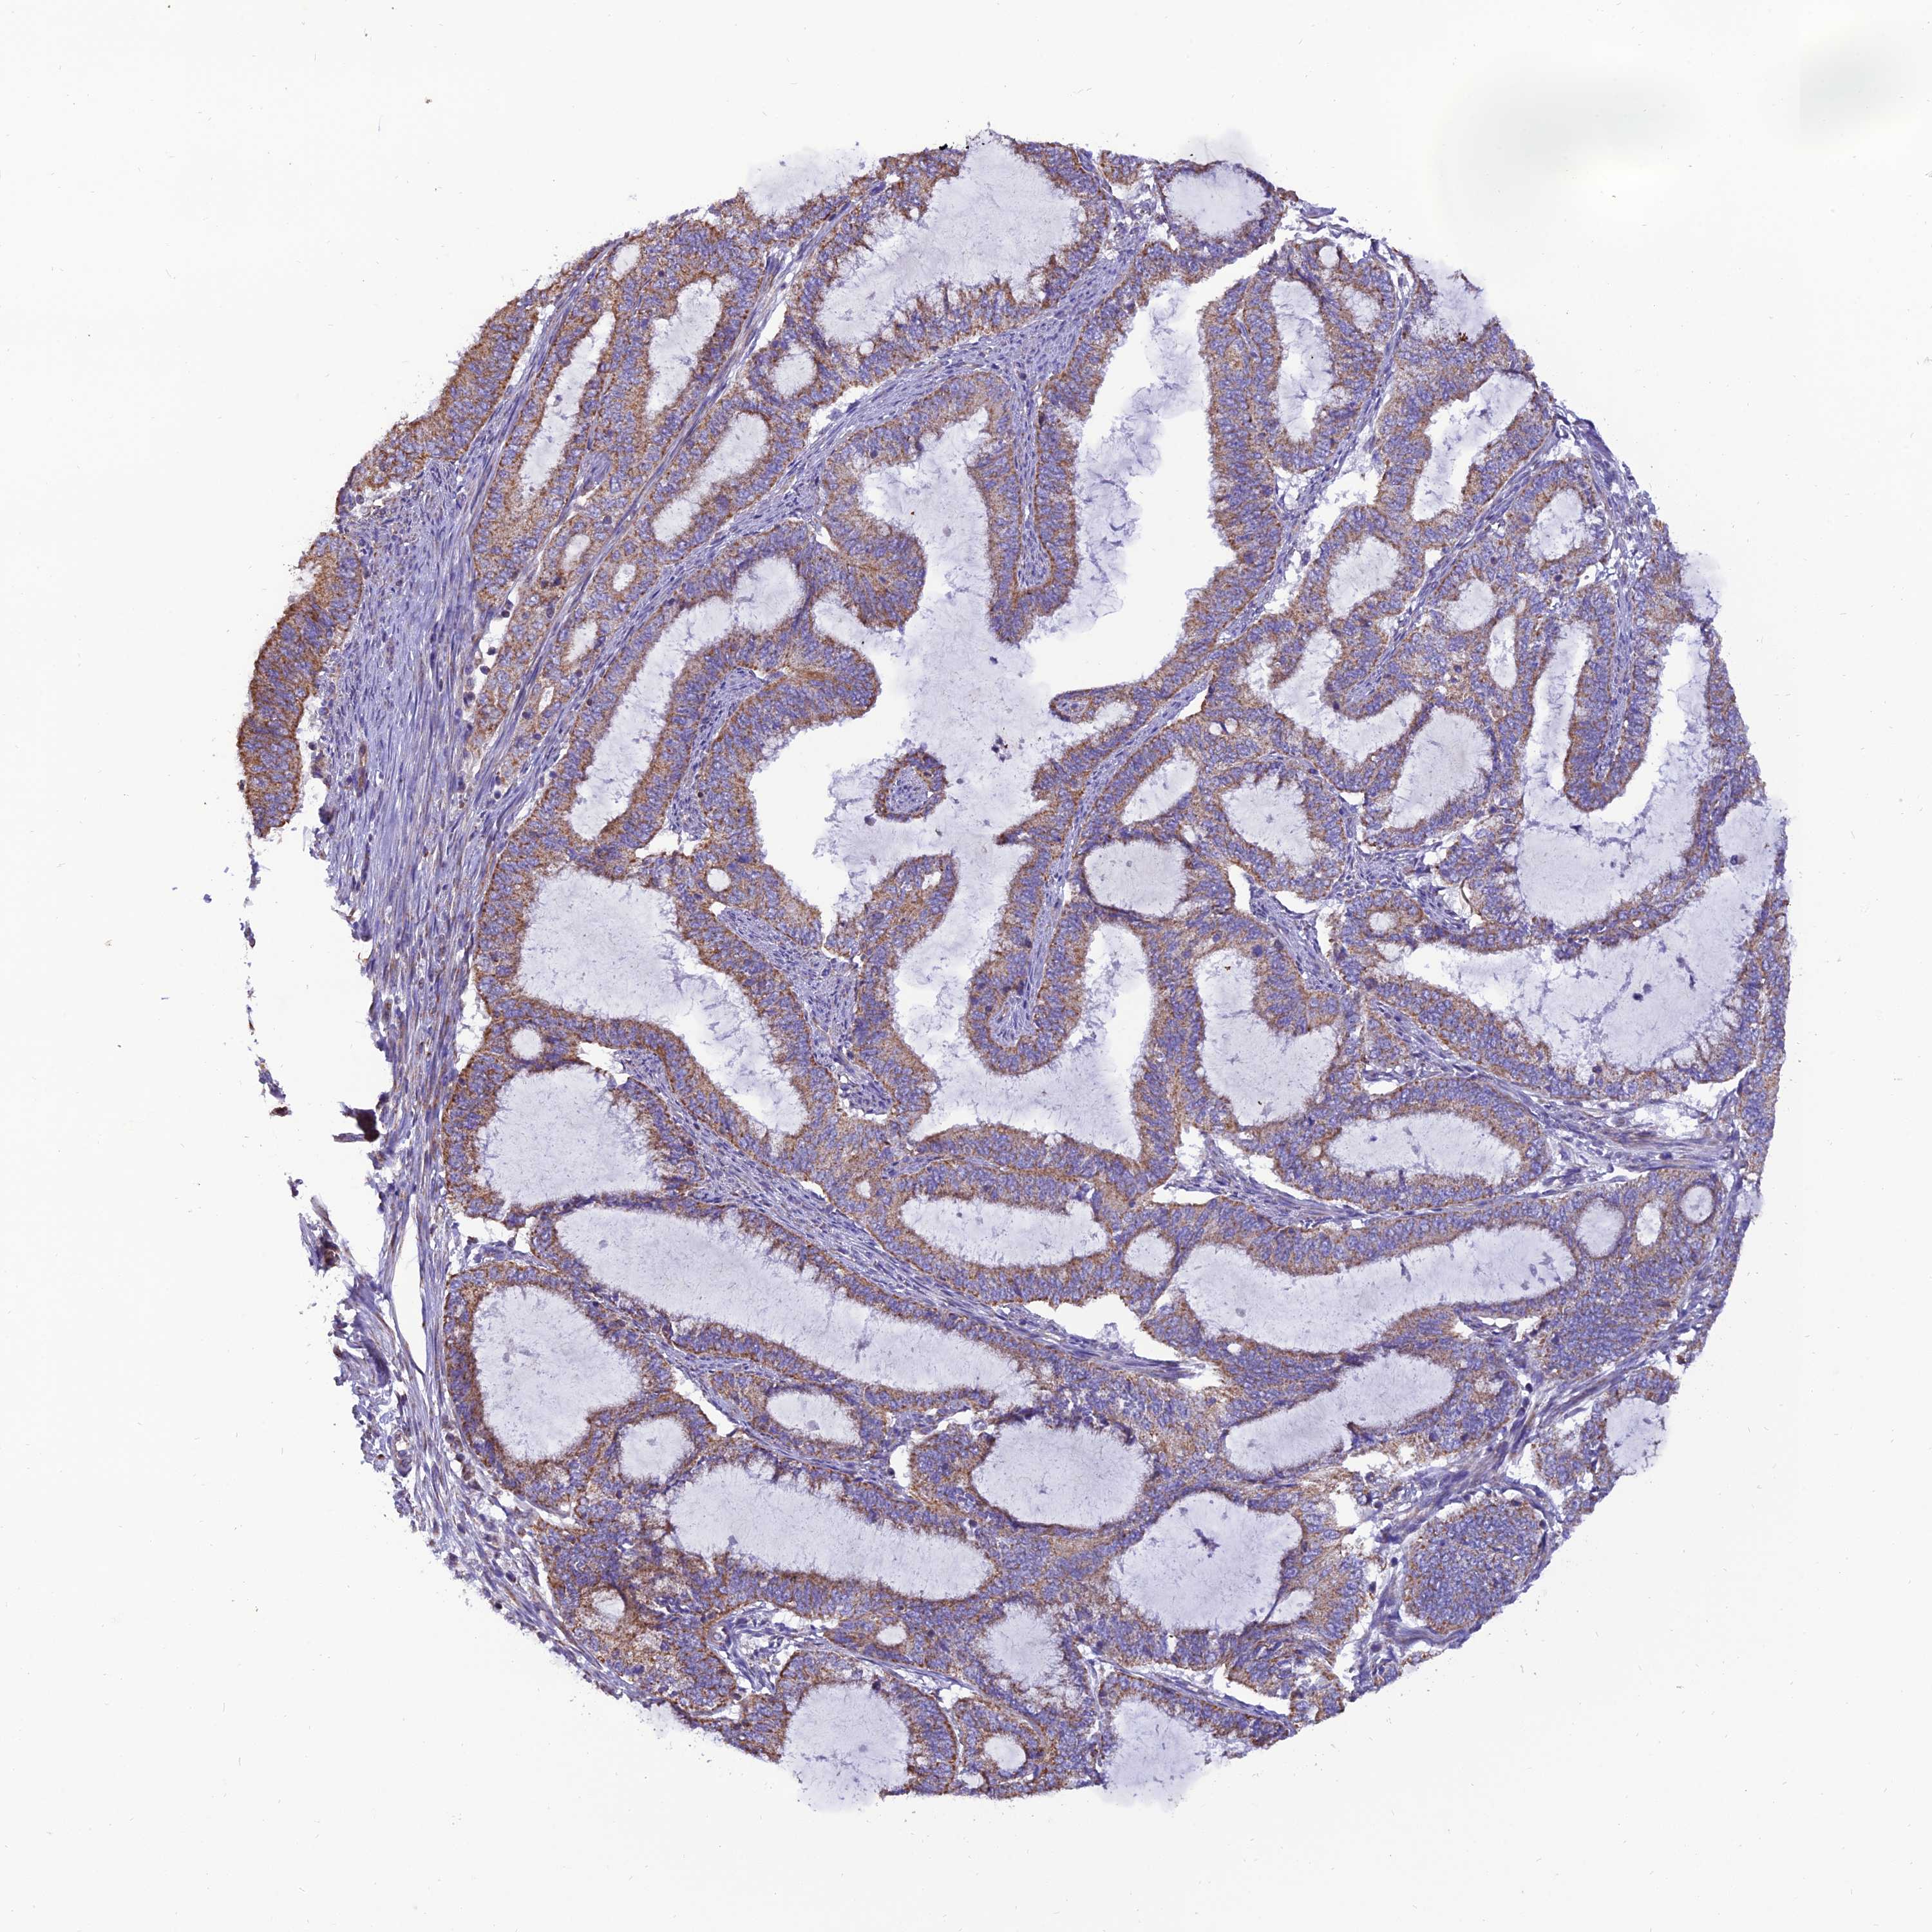

ENDOMETRIAL CANCER - Protein expressioni

A mouse-over function shows sample information and annotation data. Click on an image to view it in a full screen mode. Samples can be filtered based on level of antibody staining by selecting one or several of the following categories: high, medium, low and not detected. The assay and annotation is described here.

Note that samples used for immunohistochemistry by the Human Protein Atlas do not correspond to samples in the TCGA dataset.

Antibody stainingi

Antibody staining in the annotated cell types in the current human tissue is reported as not detected, low, medium, or high, based on conventional immunohistochemistry profiling in selected tissues. This score is based on the combination of the staining intensity and fraction of stained cells.

Each image is clickable and will lead to virtual microscopy that enables deeper exploration of all samples and also displays staining intensity scores, fraction scores and subcellular localization as well as patient and tissue information for each sample.

Antibody HPA044620

Antibody HPA058621

Staining

High

Medium

Low

Not detected

Intensity

Strong

Moderate

Weak

Negative

Quantity

>75%

75%-25%

<25%

None

Location

Nuclear

Cytoplasmic/membranous

Cytoplasmic/membranous,nuclear

Adenocarcinoma, NOS